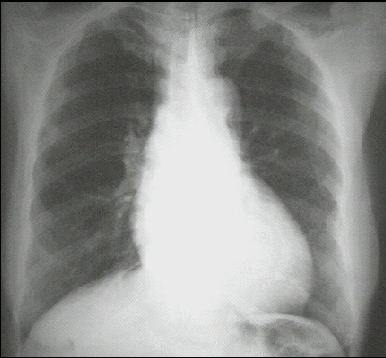

These chest X rays show left ventricular enlargement and a dilated aorta The PA view demonstrates cardiomegaly, as evidenced by a cardiothoracic ratio greater than 50%. Note also the increased inferolateral cardiac border that is consistent with ventricular enlargement due to volume overload. The ascending, transverse, and descending aortic shadows are also prominent. The lateral view shows left ventricular enlargement, as evidenced by posterior displacement of the left ventricular shadow.